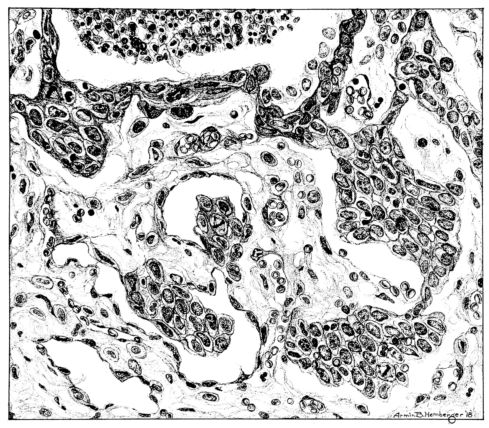

FIG. II. AUTOPSY NO. 98. DRAWING OF A SECTION THROUGH A TRACHEA SHOWING NECROTIZING HEMORRHAGIC INFLAMMATORY PROCESS OF THE MUCOSA.

The changes are less marked, perhaps, in the trachea than in its finer ramifications. The mucosa is constantly more or less destroyed and large areas, usually focal, are entirely devoid of their epithelial covering. This is replaced by a sparse exudate, composed largely of red blood cells, mucus, a small amount of fibrin, and nuclear fragments (Fig. II). It may dip into the submucosa for a short distance, but usually these indentures are associated with the ducts of the mucous glands into which the inflammatory reaction extends. A more striking feature than the exudate, however, is the edema and the congestion of the submucosa. The loose areolar tissue of the submucosa is spread widely apart, and throughout it distended blood vessels are very conspicuous. Occasionally such a vessel is broken and actual hemorrhage appears in the submucosa. Occasionally, too, the inflammation extends down the duct to the mucous gland itself, and here, also, aplastic inflammatory reaction is evident, inasmuch as the acini now stain intensely red with the cells undifferentiated from each other and specked here and there by broken remains of the dead nuclei (Fig. III). After the disease has continued for a short period, even at the end of five or six days, some regeneration of the epithelial lining may be seen (3) (Fig. IV). But despite this, the acute picture persists, and there goes on, side by side, an attempted repair characterized by epithelial regeneration and the same evidence of acute change. Since the lesion is essentially a superficial one, scars or contractures of any extent are not encountered in the trachea, even in examples of the disease that have ended fatally only after many weeks.[4]